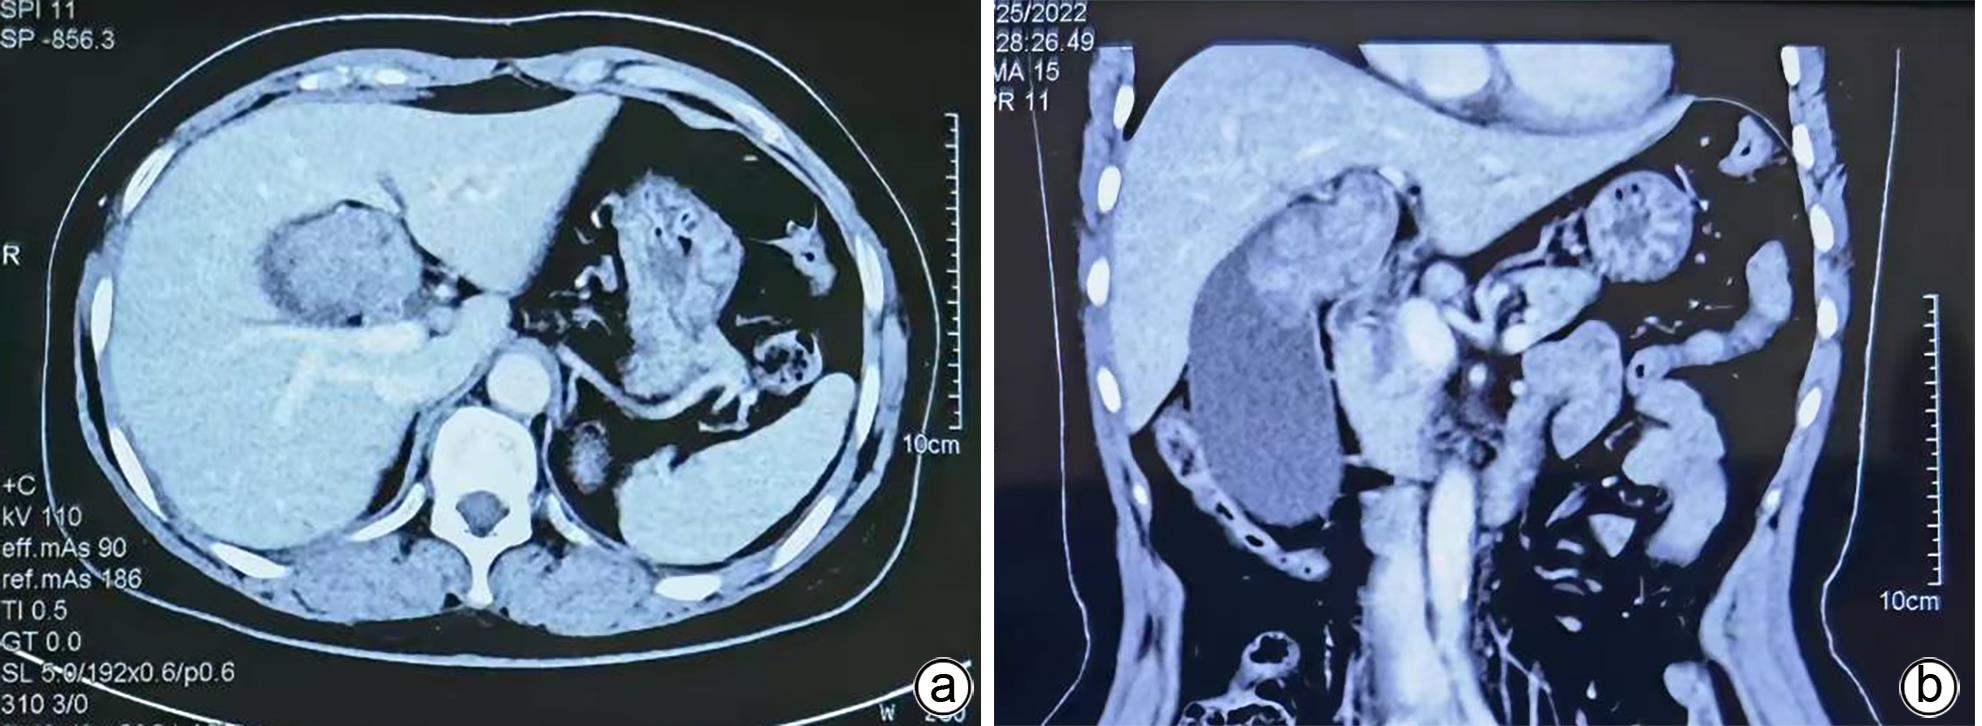

The preliminary therapeutic effect of endoscopic ultrasound-guided tissue adhesive injection with the assistance of metal clips in treatment of cirrhotic patients with gastric varices and gastric-renal shunt

Jiali MA, Zhenglin AI, Julong HU, Yu JIANG, Yuling ZHOU, Xiuxia LIANG, Hongshan WEI, Ping LI

2024, 40(4): 734-738. DOI: 10.12449/JCH240415

Abstract(1116) HTML (309) PDF (1036KB)(61)

Abstract:

Objective  To investigate the safety and efficacy of endoscopic ultrasound-guided tissue adhesive injection with the assistance of metal clips in the treatment of cirrhotic patients with gastric varices and gastric-renal shunt (GRS).  Methods  The patients who attended Beijing Ditan Hospital, Capital Medical University, due to liver cirrhosis and gastric varices from February to June 2023 were enrolled, and all patients were confirmed to have GRS and received endoscopic ultrasound-guided tissue adhesive injection with the assistance of metal clips. The primary evaluation index was alleviation or disappearance of varicose veins after surgery, and the secondary evaluation indices were surgical completion and complications.  Results  A total of 11 patients were enrolled in this study, among whom there were 7 male patients and 4 female patients, with a median age of 55 years. Of all patients, 1 had Child class A liver function, 7 had Child class B liver function, and 3 had Child class C liver function. The maximum (median) diameter of the shunt was 8 mm, and the minimum (median) diameter of the shunt was 4 mm. The median blood flow velocity of the target vessel was 11 cm/s before treatment and 5 cm/s after occlusion with metal clips. The median amount of tissue adhesive injected was 2 mL, and the amount of lauromacrogol used was 1 mL. Disappearance of blood flow signals was observed in all patients after surgery (100%), and the success rate of surgery was 100%. No patient experienced rebleeding after follow-up for 6 weeks. Gastroscopy at 1 month after surgery showed that gastric varices were eradicated or almost disappeared in 9 patients and were alleviated in 2 patients.  Conclusion  Endoscopic ultrasound-guided tissue adhesive injection with the assistance of metal clips is a feasible, safe, and effective treatment method for cirrhotic patients with gastric varices and GRS.